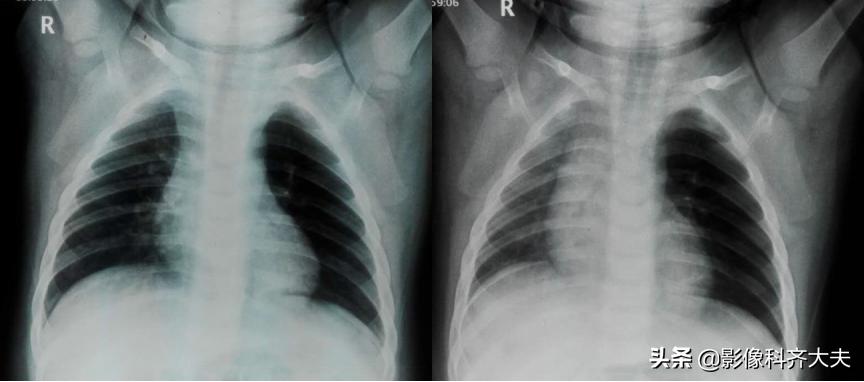

病例2、病史:患儿,男、1岁9个月,咳喘20天。家属否认异物吸入史。

图为正位普通X线片,显示左侧明显肺气肿改变,提示左侧支气管异物可能,因家属否认异物吸入,遂进一步做CT确诊。

CT冠状位重建明确显示左侧自气管阻塞,有明确异物的存在,红色箭头所示。